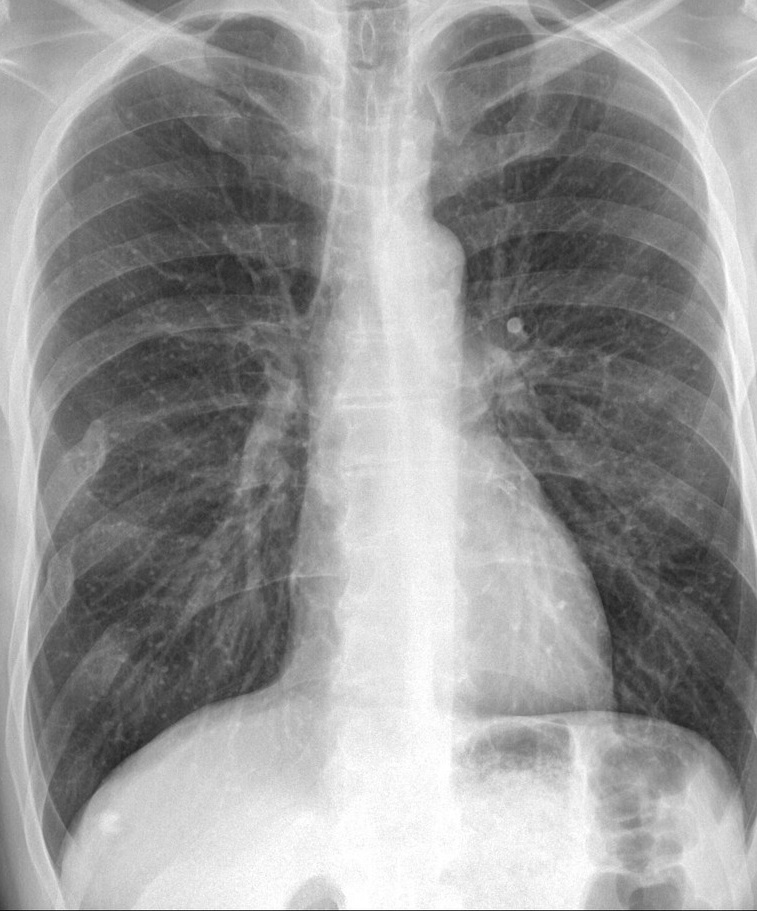

Figure 6 presents image examples for each class retrieved from the RYDLS-20 database. It is worth to mentioning that we have no further information concerning the CXR images with regarding the CXR machine used to take the image, as well as the origin, age and ethnicity of the people whose these images belong to.

Refer to caption

(a) Normal.

(b) COVID-19.

(c) SARS.

(d) MERS.

(e) Pneumocystis.

(f) Streptococcus.

(g) Varicella.

Figure 6: RYDLS-20 image samples.